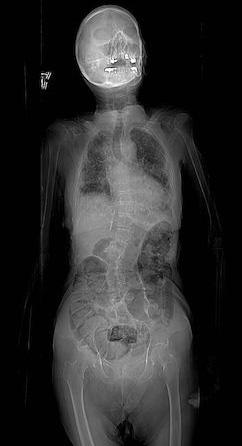

The image shown here is the scout film of cadaver 33448. Notice how the spine has a slight C-shaped curve involving the lower thoracic and lumbar vertebrae. The curve is convex toward the patient's left.

The movie shown here is a CT scan of the same cadaver. The cervical spine can be found at time= 40-45, K8. Advance the movie forward (moving the cross section further down the body) while following the spine. The transition from cervical spine to thoracic spine occurs at time= 48. This transition is marked by the appearance of the 1st and 2nd ribs coming off of the T1 and T2 vertebrae. Continue keeping track of your level on the spine by counting ribs as they come off the vertebrae as you advance the movie forward. Notice that around T10, time= 60, the spine begins shifting to the patient's left (remember: the orientation of CT scans places the viewer at the foot of the patient looking toward the head, so the patient's left is on the viewer's right). From T10- L5 the spinal column is seen to deviate to the left and then come back to center just as the iliac crests come into view. You will also notice that the spinal column moves anteriorly while viewing L1-L5; this is normal lordotic curving of the lumbar spine.